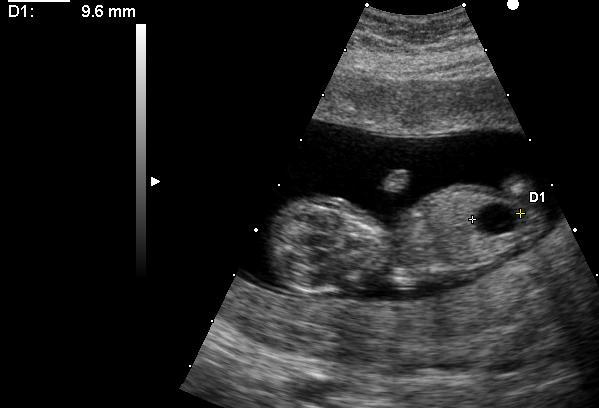

Méga vessie chez un embryon porteur d'une trisomie 21.Megacystis in embryo with Down'syndrome.